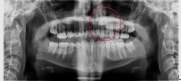

Dientes impactados

Los dientes impactados pueden provocar reabsorción radicular, requerir intervención quirúrgica para exponerlos y alinearlos en el arco, o extracción con una oclusión final comprometida.